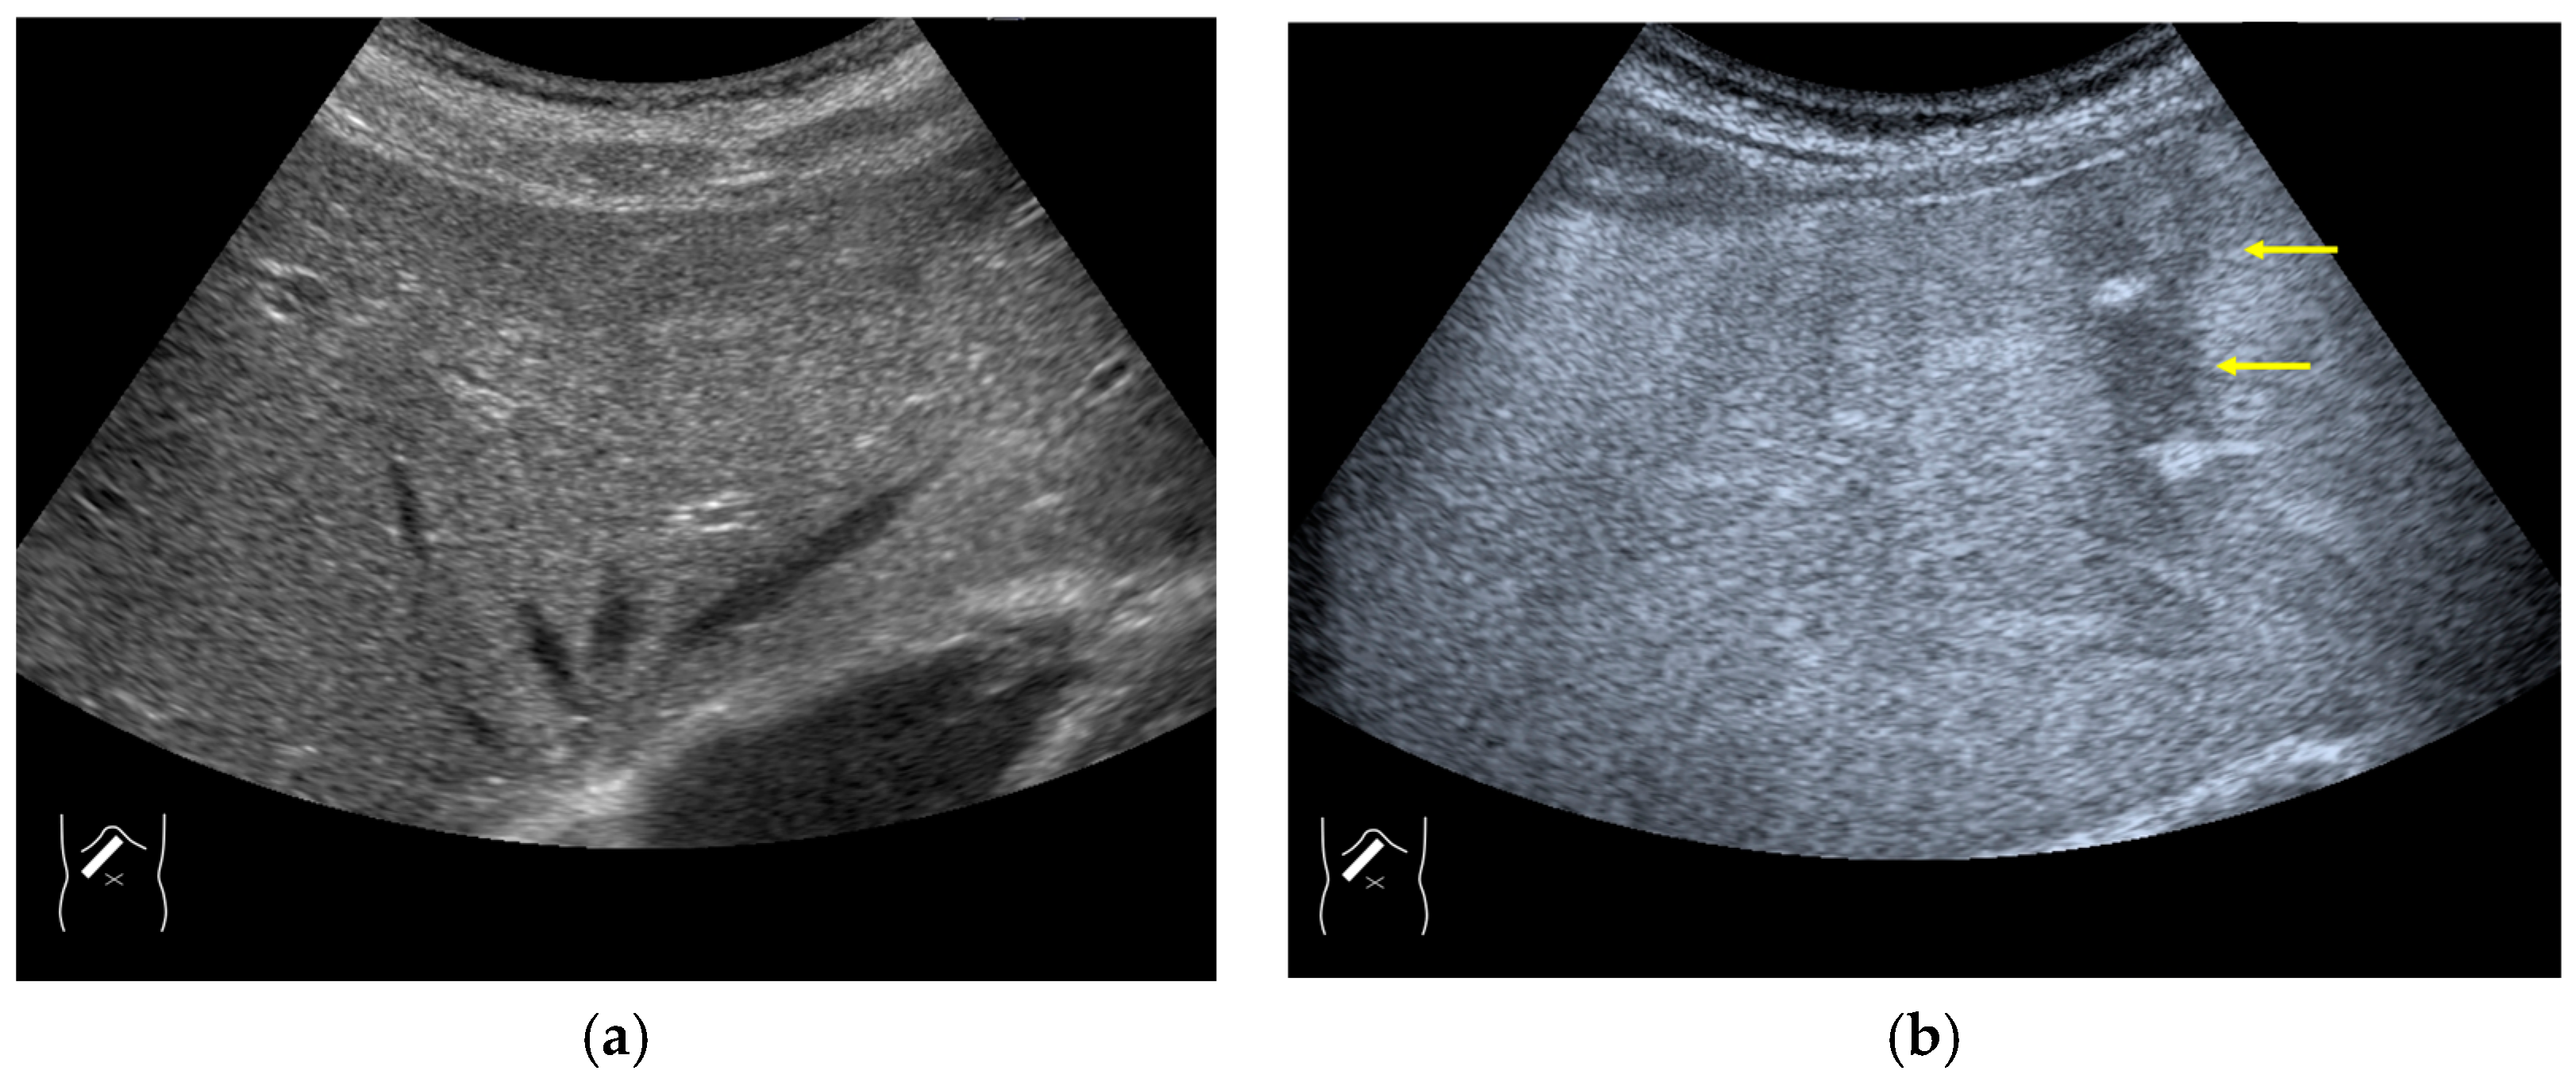

3.1.2. Attenuation Artifacts

3.1.3. Range-Ambiguity Artifacts (RAAs)

- Naganuma, H.; Ishida, H.; Funaoka, M.; Fujimori, S.; Okuyama, A.; Odashima, M.; Takeuchi, S.; Hanaoka, A. Mobile echoes in liver cysts: A form of range-ambiguity artifact. J. Clin. Ultrasound 2010, 38, 475–479. [Google Scholar] [CrossRef]

- Naganuma, H.; Ishida, H.; Nagai, H.; Ogawa, M.; Ohyama, Y. Range-ambiguity artifact in abdominal ultrasound. J. Med. Ultrason. 2019, 46, 317–324. [Google Scholar] [CrossRef] [PubMed]